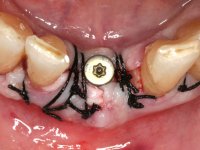

• Two months after implant placement and guided-bone regeneration, initiate the construction of a metal-ceramic fixed partial denture with two elements screwed on the dental implant.

With the implant osteo-integrated with did an impression (open-tray technique) and the dental technician started the construction of a gold framework. The use of an abutment made of a gold alloy allowed us to do a framework with a perfect fit.